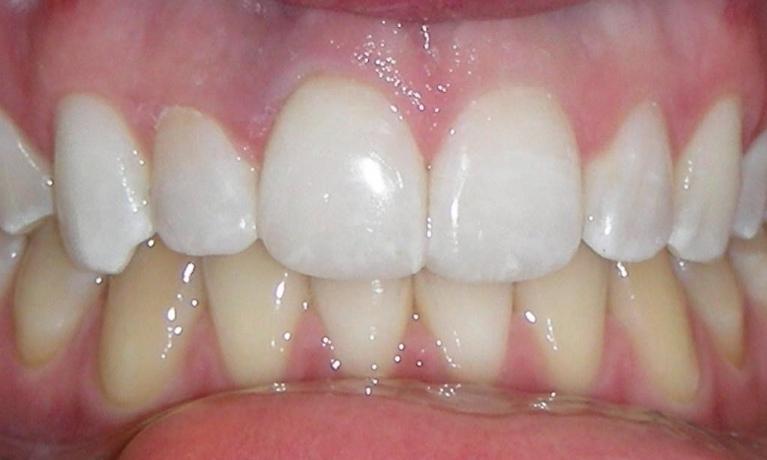

Repair of Tooth Wear with Composite Resin

Cervical abrasion, or excessive wear of the exposed root structure can be the result of many factors including gum recession, and aggressive brushing. Besides being unsightly, it can lead to cold sensitivity and weakening of the tooth structure. Composite resin restoration is a conservative procedure that can be completed in one visit with minimal or no drilling of the existing teeth. It can eliminate sensitivity, strengthen the teeth, and restore the beauty of the smile.